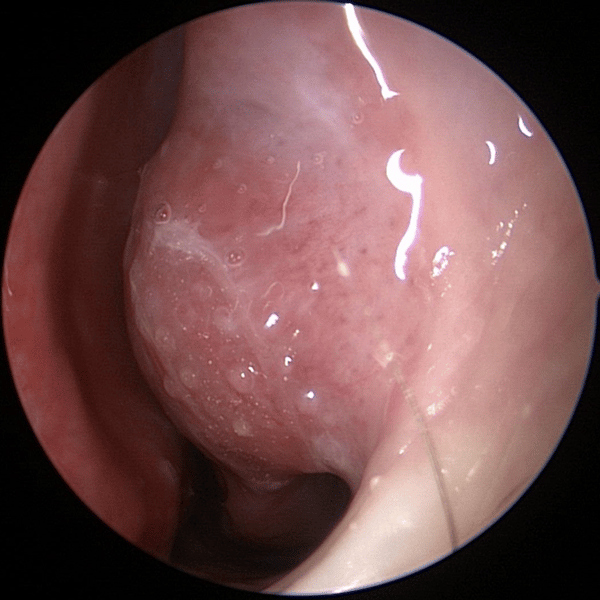

visão endoscópica Rinite